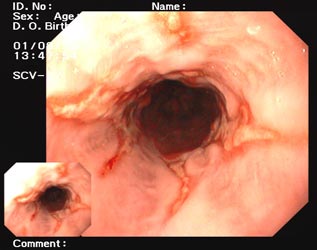

Die Diagnose wird durch die Erhebung (Anamnese) des typischen Beschwerdebildes beim Arzt gestellt. Der behandelnde Arzt trifft mit dem Patienten zusammen aufgrund der Beschwerden die Entscheidung zu weiterführenden diagnostischen Maßnahmen. Die wichtigste Maßnahme ist die Speiseröhren-Magenspiegelung (Ösophago-Gastro-Duodenoskopie). Eine Spiegelung ist immer dann notwendig, wenn die Beschwerden (schmerzhaftes Schlucken, also Dysphagie), Blutung (Kaffeesatzerbrechen), Husten, Hochwürgen von Speise (Regurgitation) und Behinderung oder Steckenbleiben der Speise auf eine Komplikation hindeuten oder wenn die Beschwerden auf einen ausreichenden Behandlungsversuch nicht ansprechen. Bei häufigen und lange bestehenden Beschwerden ist ebenfalls eine Spiegelung dringend anzuraten.

Man spricht von einem Barrett-Ösophagus, wenn sich im unteren Teil der Speiseröhre statt Plattenepithel Magenschleimhaut (Zylinderepithel) befindet. Aus diesem Grunde kann diese Diagnose nur durch eine Spiegelung mit Gewebeprobenentnahme gestellt werden. Der Barrett-Ösophagus hat wegen seines Potenzials der Entstehung von Krebs in den letzten Jahren verstärkte Aufmerksamkeit erfahren. Das Risiko, Krebs in der unteren Speiseröhre zu entwickeln, ist dann besonders hoch, wenn sich in den Gewebeproben Veränderungen von Krebsvorstufen (Dysplasie) finden. Nach Forschungsergebnissen scheint das längere Vorhandensein einer Refluxerkrankung zur Entstehung des Barrett-Ösophagus mit beizutragen.